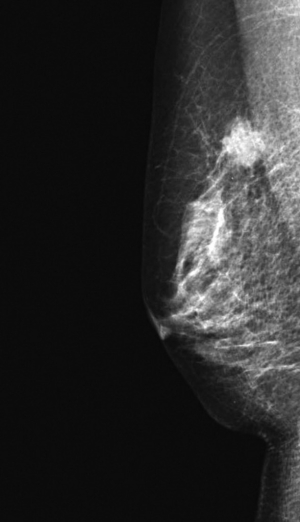

65歳の女性。検診のマンモグラフィで異常陰影を指摘され来院した。右乳房に長径2cm の腫瘤を触知する。腫瘤は円形、弾性硬で、可動性は良好で圧痛を認めない。乳頭からの分泌物を認めない。

マンモグラムを別に示す。乳房超音波検査で辺縁不整な低エコー腫瘤像を認める。